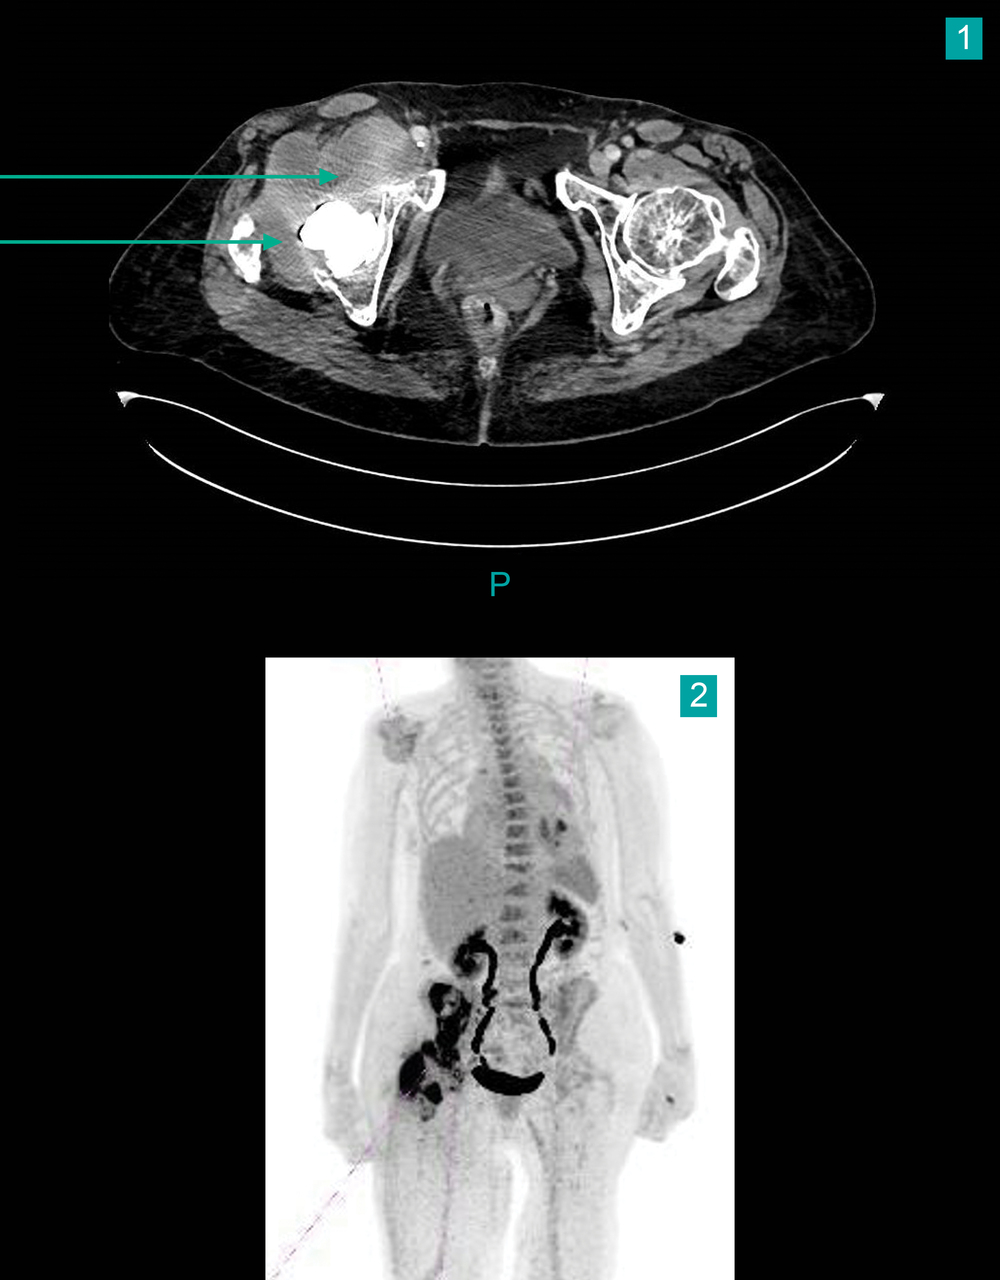

Un scanner thoraco abdomino pelvien est demandé (fig. 1), complété par une tomodensitométrie à émission de positons (TEP) scan 18 FGD (fig. 2).

Le scanner montre une collection périprothétique étendue dans le muscle psoas iliaque, de 14 cm de hauteur et de 4 cm de largeur maximale.

Le TEP-scan 18-FDG objective un hypermétabolisme périprothétique de la prothèse totale de hanche droite, prédominant au versant acétabulaire et péricervical, avec infiltration des parties molles.